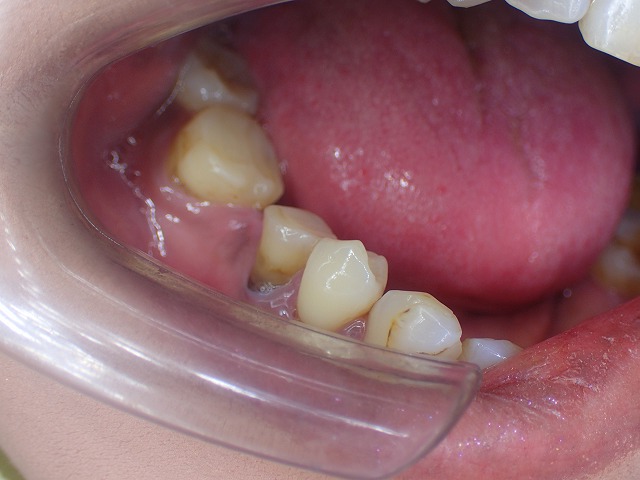

奥歯の欠損を放置していたので

顎の変形が起こり 後ろの歯が前に向いています。

顎の骨が折れるように変形しているからです。

奥歯も放置のまま

前歯には欠損している歯が2本あります。